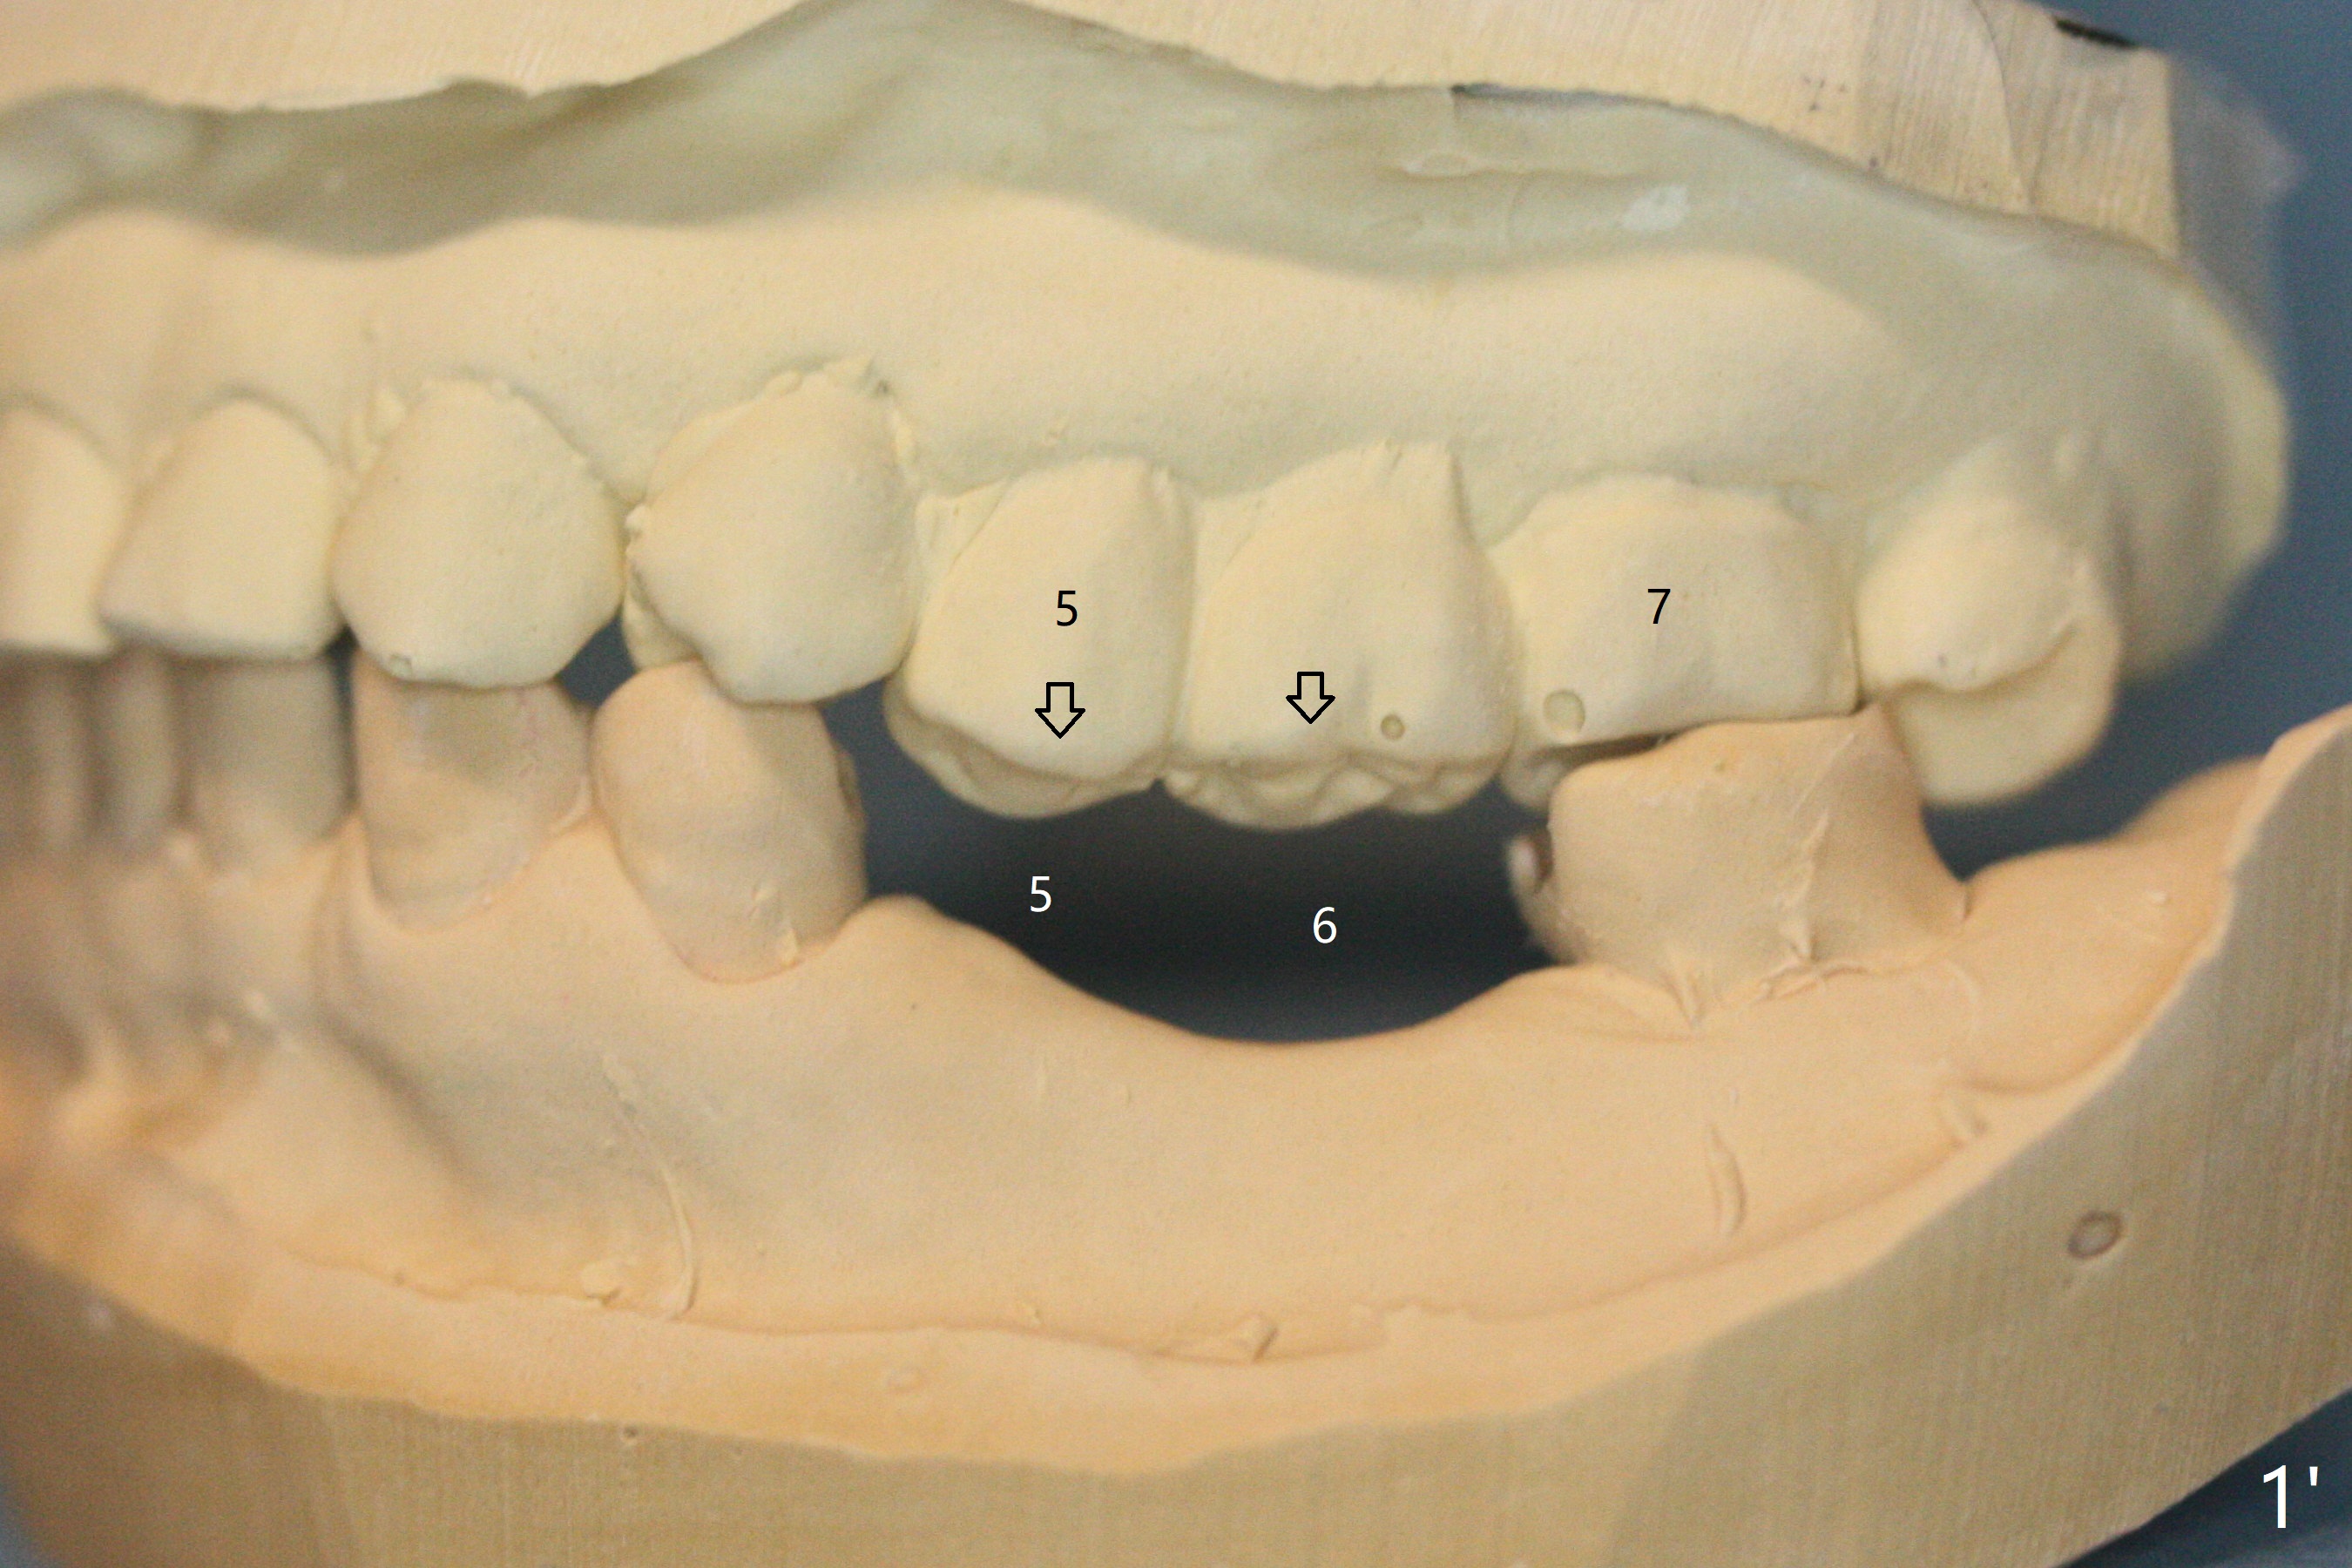

57岁女缺失四个下牙(图一),由于保险限制,先考虑左边种植(图二,三),主要问题是牙槽嵴狭窄(不过左上牙桥做的太长了,尤其是5,6(图一'),造成下面垂直距离缩短,修复困难。总之,她的牙齿显得短小)。牙槽嵴狭窄处理方法:切口,使用导板用bone trimmer和最细钻头(point drill或者2.2毫米)钻洞(图四:黑圆圈),到深度,然后用圆形骨锯在牙槽嵴顶部劈开(弯曲红线),必要时做三个垂直骨切口(图六),徒手利用旋转式骨扩张器,或者骨凿,推开颊侧骨板。也准备外科钻头(新的)。放置导板和钻头除去舌侧骨板,最后在5,6分别植入3.0 或者3.5毫米,4.0或者4.5毫米植体。如果初步稳定性好,即刻修复,主要防止7继续近中倾斜,必要时,7近中(图一*)植骨。抽血制备两个PRF膜和粘性骨块。